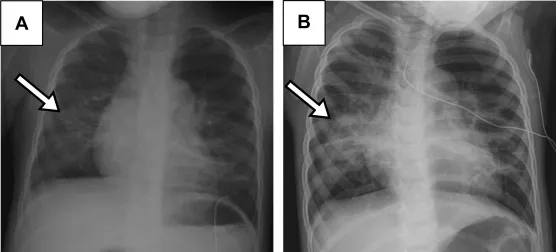

Images of Human Metapneumovirus Infection